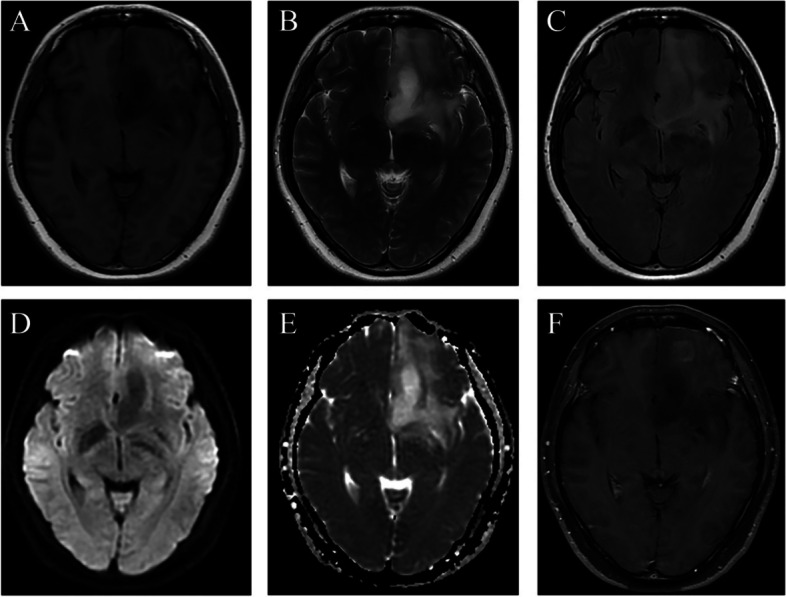

Results: Twenty patients, including 7 males (55%) and 13 females (45%), with a mean age at diagnosis of 37.9 years (range, 28-53 years) underwent operative intervention for APS. Headaches and dizziness were the most common preoperative symptoms in the majority patients (14, 70%). Based on radiological features of MRI, the APS was classified into two subtypes, type A and type B. Seven patients (40%) in type A indicated a clear tumor margin, while 13 patients (60%) in type B showed an ill-defined margin. The surgical approach including frontal, temporal, and coronal frontal incisions for type A and type B tumors, respectively. Three patients in type A received total resection, while one patient in type B were total resected. Pathologically, 12 cases (60%, 12/20) were diagnosed as astrocytoma and 8 cases (20%, 8/20) were oligodendroglioma. Meanwhile, 17 cases (85%, 17/20) had MGMT promotor methylation.

Conclusion: In this study, we performed the first systematic research of patients with APS glioma. Most of patients with APS presented headaches and dizziness symptoms. The APS glioma was further divided into two major radiological subtypes with relevant different surgical approaches. The APS glioma in type A were more likely to receive total resection.